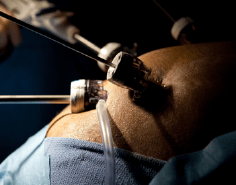

Cirugía Laparoscópica

La Cirugía por abordaje Laparoscópico o Cirugía de Mínima Invasión, es una técnica quirúrgica especializada en la que a través de pequeñas incisiones se introduce una lente y diferentes pinzas e instrumentos por medio de los cuales se llevan a cabo los diferentes procedimientos quirúrgicos. Las principales ventajas de la Cirugía Laparoscópica son:

Este tipo de procedimiento lo realizamos en diferentes centros hospitalarios, por lo que los precios se ajustan a tu presupuesto o si cuenta con seguro de gastos médicos nos ajustamos al tabulador de tu compañía de seguros.